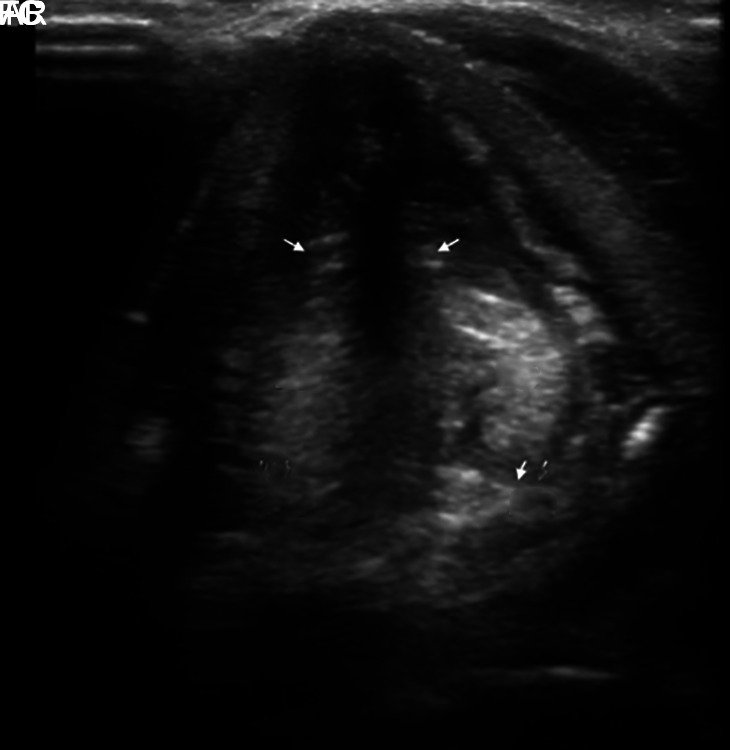

Materials and methods: This prospective observational study was conducted in the burns intensive care unit (ICU) of a tertiary care hospital. Bedside airway USG was performed to evaluate vocal cord (VC) width for edema and other airway parameters, including tongue thickness, pre-epiglottis space depth, inter-arytenoid distance, epiglottis-to-midpoint of VC, distance between the true VCs, distance between the false VCs, tracheal wall thickness, and tracheal air column width. Fiberoptic bronchoscopy was then performed to assess airway involvement, and findings were correlated with USG at the VC level.

Results: About 51 patients were included. Airway USG assessment was able to predict the VC edema, correlating with FOB findings in 30 patients. Ultrasound showed a sensitivity and specificity of 85.2 and 81.3%, respectively, with a positive and negative predictive value of 90.9 and 72.2%, respectively, for assessing airway edema at the level of VC. The mean right and left VC widths were 21.15 ± 9.52 mm and 22.03 ± 9.52 mm, respectively, in patients with VC edema. The pre-epiglottis space in patients with (n = 33) vs without VC edema (n = 18) was found to be statistically significant (14.5± 5.64 mm vs 10.87 ± 4.36 mm; p = 0.02).